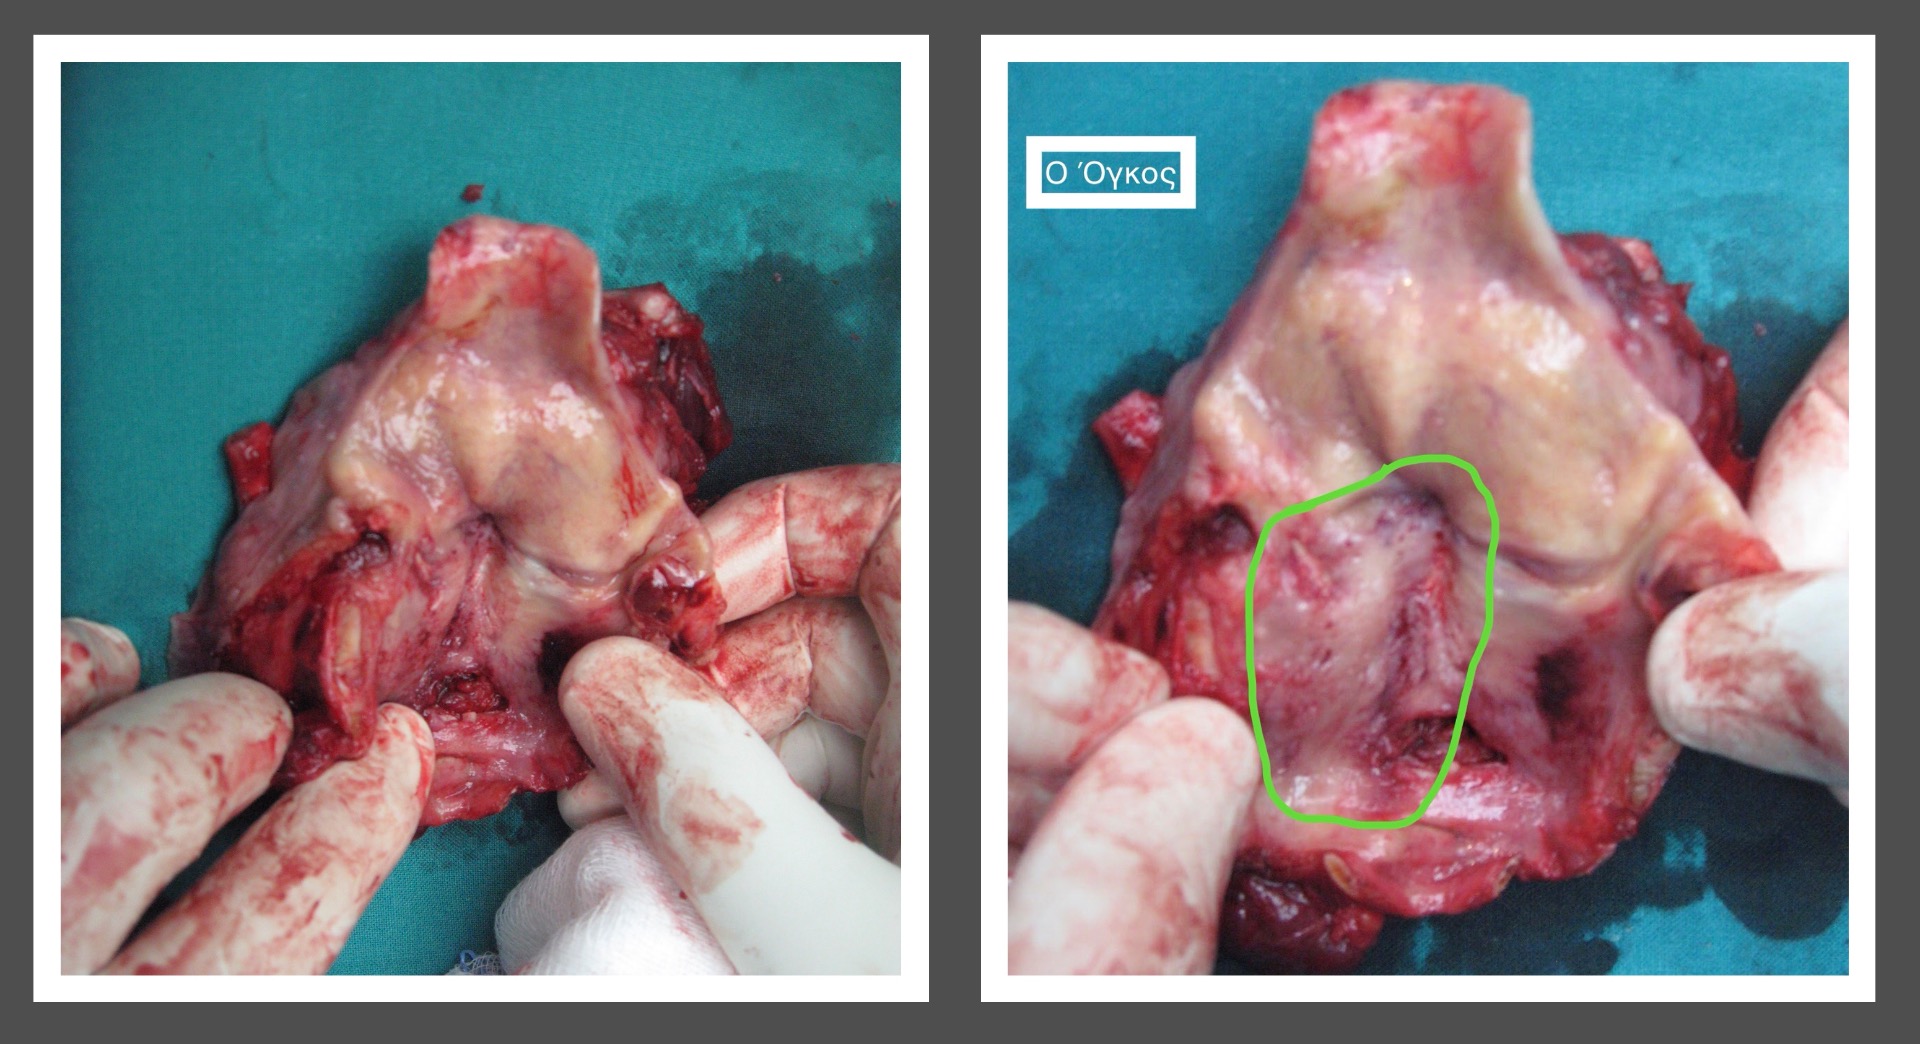

Θα ακολουθήσει η παράθεση κάποιων περιστατικών μου

Περιστατικό 1

Περιστατικό 2

Περιστατικό 3

Περιστατικό 4

Περιστατικό 5